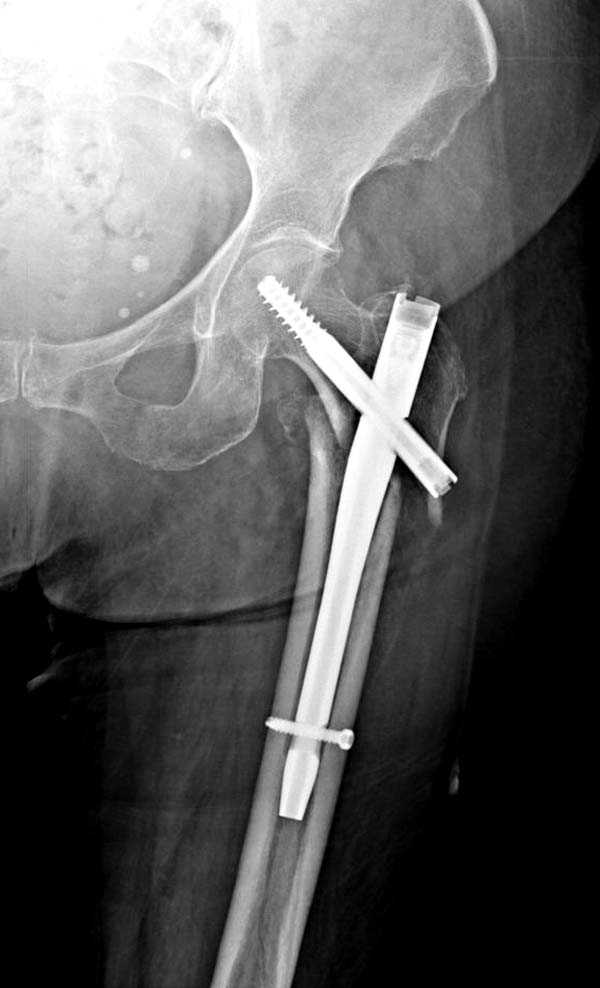

Здесь представлен случай, где в послеоперационном периоде обнаружена техническая ошибка, Gamma 3 установлен с нарушением методики. Больная в 91 лет, прооперирована через день после поступления и выписана через 48 часов.

При первом послеоперационном поликлиническом осмотре больная предъявила жалобы на боли в бедре. В серийных снимках обнаружен продольный перелом верхнего отдела бедра.

Считаем, что техническая ошибка произошла во время установки гвоздя, когда рассверливанию канала не уделили должного внимания. Канал остался узковат, и гвоздь был забит с силой. Полная нагрузка конечности приостановлена на две недели, и боли в конечности изчезли. Больная начала нагрузку и перелом срастается.-- Djoldas Kuldjanov, M.D.Associate ProfessorDepartment of Orthopedic SurgerySt. Louis University

I have a different interpretation of this case. I suspect you did not tighten the set screw all the way in order to allow sliding of the lag screw and fracture fragment compression, as you would for a standard intertrochanteric hip fracture. This is a reverse obliquity fracture, so the result is migration of the proximal segment. I doubt reaming the canal would have prevented this. Had the set screw been fully tightened, there would be no postoperative fragment motion.

Мне тоже представляется, что это не единственная проблема. Продольные трещины заживают легко и быстро. Интересно, почему увеличился варус и

появилась медиализация дистального отломка.

Мне думается, что варусное положение проксимального отломка на последующих снимках не более чем проекционный феномен. Раскол же диафиза вдоль, наверняка, связан с чрезмерно насильственным введением штифта. Вообще, при реверсивных, да и обычных вертельных переломах, многие давно отказались от короткой Гаммы в пользу long-версии. Но в любом случае надо быть на 100 уверенным в подготовке канала.